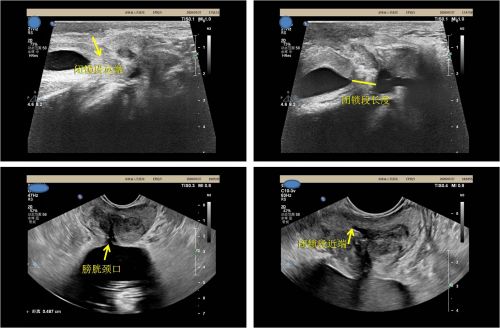

与尿道造影相比,尿道超声影像学检查可动态观察尿道充盈及排空情况。

曾铭强博士仔细询问病史并结合检查资料判断,老人从高处摔下时骑坐在梯子上造成骑跨伤,导致尿道断裂。完善相关检查后,曾铭强博士联合超声科为患者进行尿道超声影像学检查。7月26日,又为患者进行了膀胱软镜检查,在距离尿道外口12cm处发现狭窄。

“尿道修复重建可以让尿道狭窄、闭锁的患者恢复正常排尿功能,维持正常生理结构,保持正常性生活”,曾铭强博士介绍,近年来,由于各种意外事故导致尿道损伤的发病率日益增加,患者在做尿道修复重建手术前,采取经会阴联合经直肠途径尿道超声检测,可以动态观察尿道闭锁的长度、瘢痕的程度,以及前后尿道与周围组织的关系,能较好地评估手术的难度,了解尿道损伤有无并发症,这一技术的开展将造福众多尿道狭窄、闭锁患者。